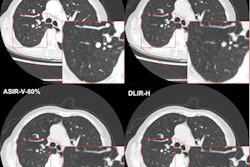

A 57-year-old man who underwent coronary CTA using two-breath-hold subtraction technique to assess patency of coronary artery stent. (A) Conventional hybrid interactive reconstruction (HIR) image and (B) conventional deep-learning reconstruction (DLR) image show blurred appearance of proximal aspect of stent (arrow). (C) Subtraction HIR image and (D) subtraction DLR image show discrete region of hypoattenuation at proximal aspect of stent (arrow). Both readers provided a diagnosis of in-stent restenosis only for subtraction HIR and subtraction DLR. Diagnostic confidence score for the four methods for reader 1 was 2, 2, 3, and 4, respectively, and for reader 2 was 1, 2, 3, and 3, respectively. Patient subsequently underwent invasive catheter angiography. Fluoroscopic imaging obtained (E) before and (F) after contrast media injection demonstrate in-stent restenosis of proximal aspect of stent (arrow). All images courtesy of the American Journal of Roentgenology.Two cardiothoracic radiologists, with five and eight years of post-training experience, respectively, read the exams in a blinded manner over two sessions, separated by one month, on a Syngo.via VB10 workstation (Siemens Healthineers). In each session, the radiologists independently reviewed either the conventional hybrid iterative reconstruction or conventional hybrid deep learning-reconstruction images and also a simulated assessment of combined conventional and subtraction images for one of the two reconstruction techniques.